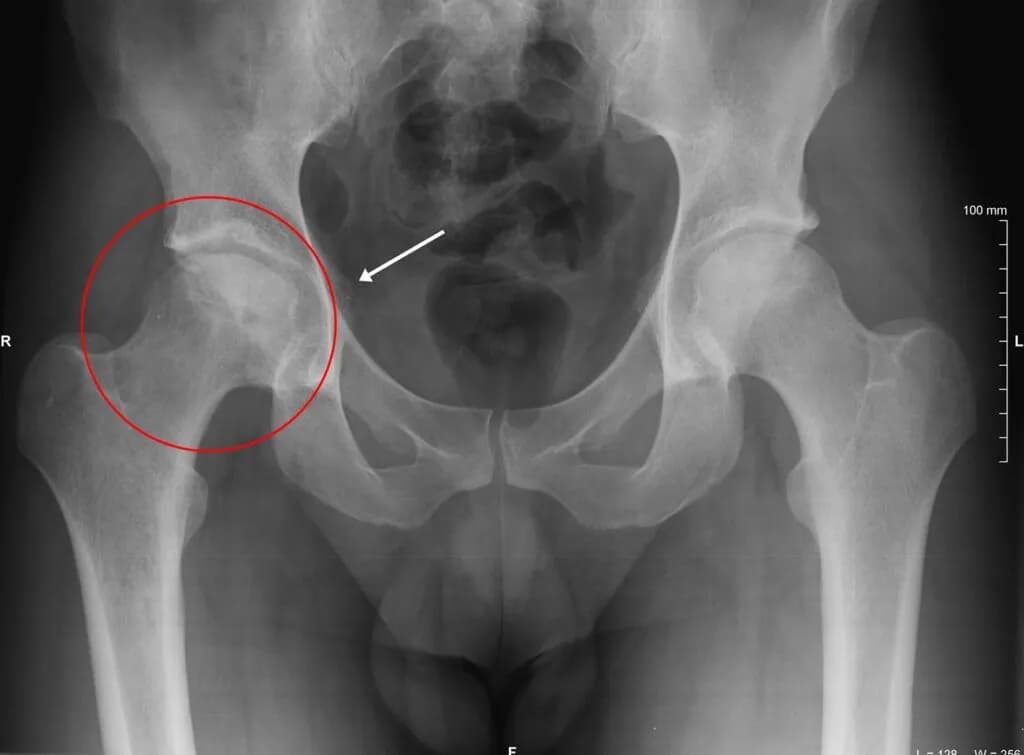

Jakie badania diagnostyczne są zalecane?

Rozpoczęcie leczenia skręcenia stawu biodrowego wymaga dokładnej diagnozy. Lekarze zazwyczaj zalecają wykonanie następujących badań:

| Rodzaj badania | Cel badania |

| RTG | Ocena kości i wykrycie złamań. |

| MRI | Dokładna ocena tkanek miękkich i więzadeł. |

W oparciu o wyniki badań lekarz podejmuje decyzję o dalszym leczeniu. Właściwa diagnoza jest kluczowa dla skutecznego wyleczenia.